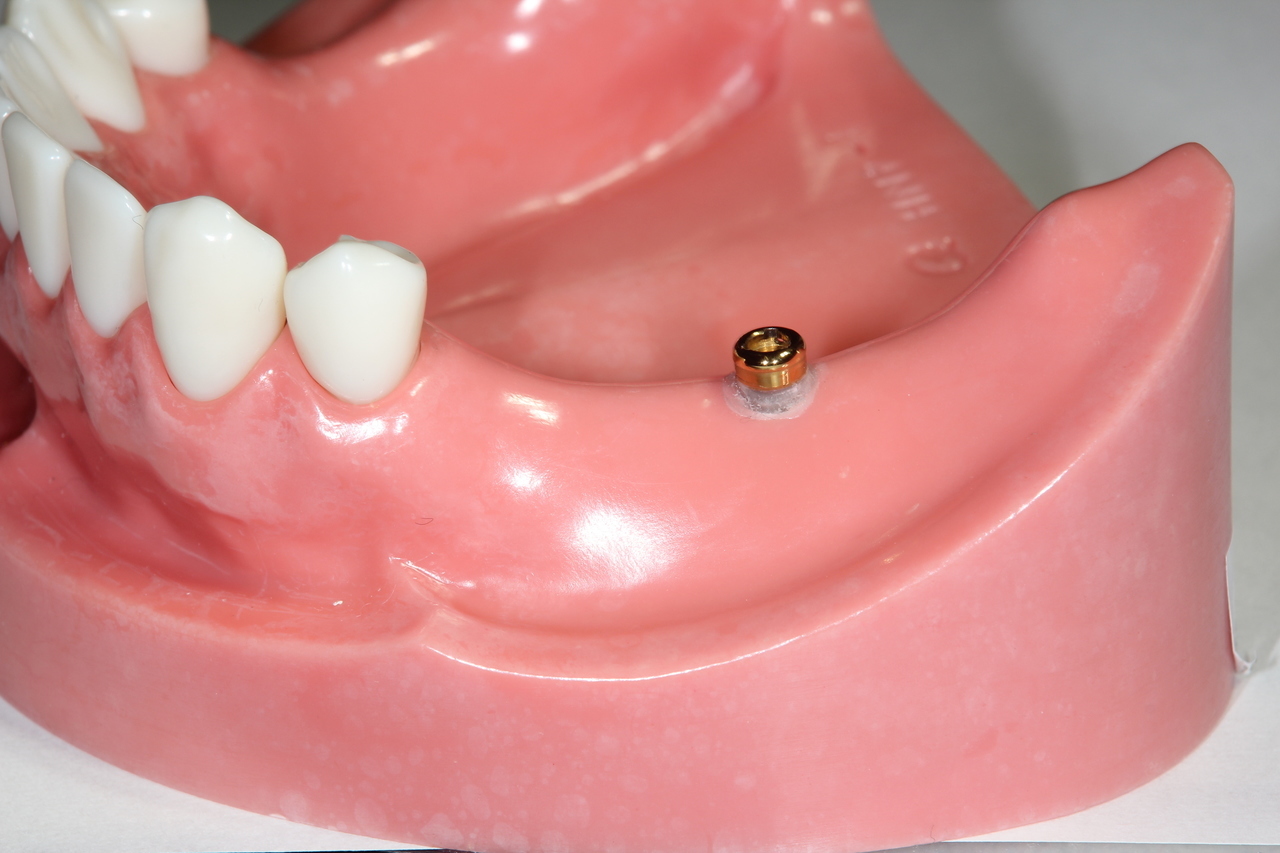

インプラントオーバーデンチャー<ロケータータイプ> (沼津市在住 男性)

インプラントを埋め込み、固定用のロケーターを装着し、入れ歯をしっかりと固定する治療法です。

少ない本数でがっちり噛める治療法です。取り外し可能でしっかり固定できるので、入れ歯の誤飲の心配がなく、手入れがしやすいので寝たきりになっても安心に使用出来ます。

しっかり噛むことで踏ん張りがきくので転んで骨折するリスク回避にもなります。

● オーバーデンチャーを外した状態

● オーバーデンチャーを付けた状態

インプラントオーバーデンチャー